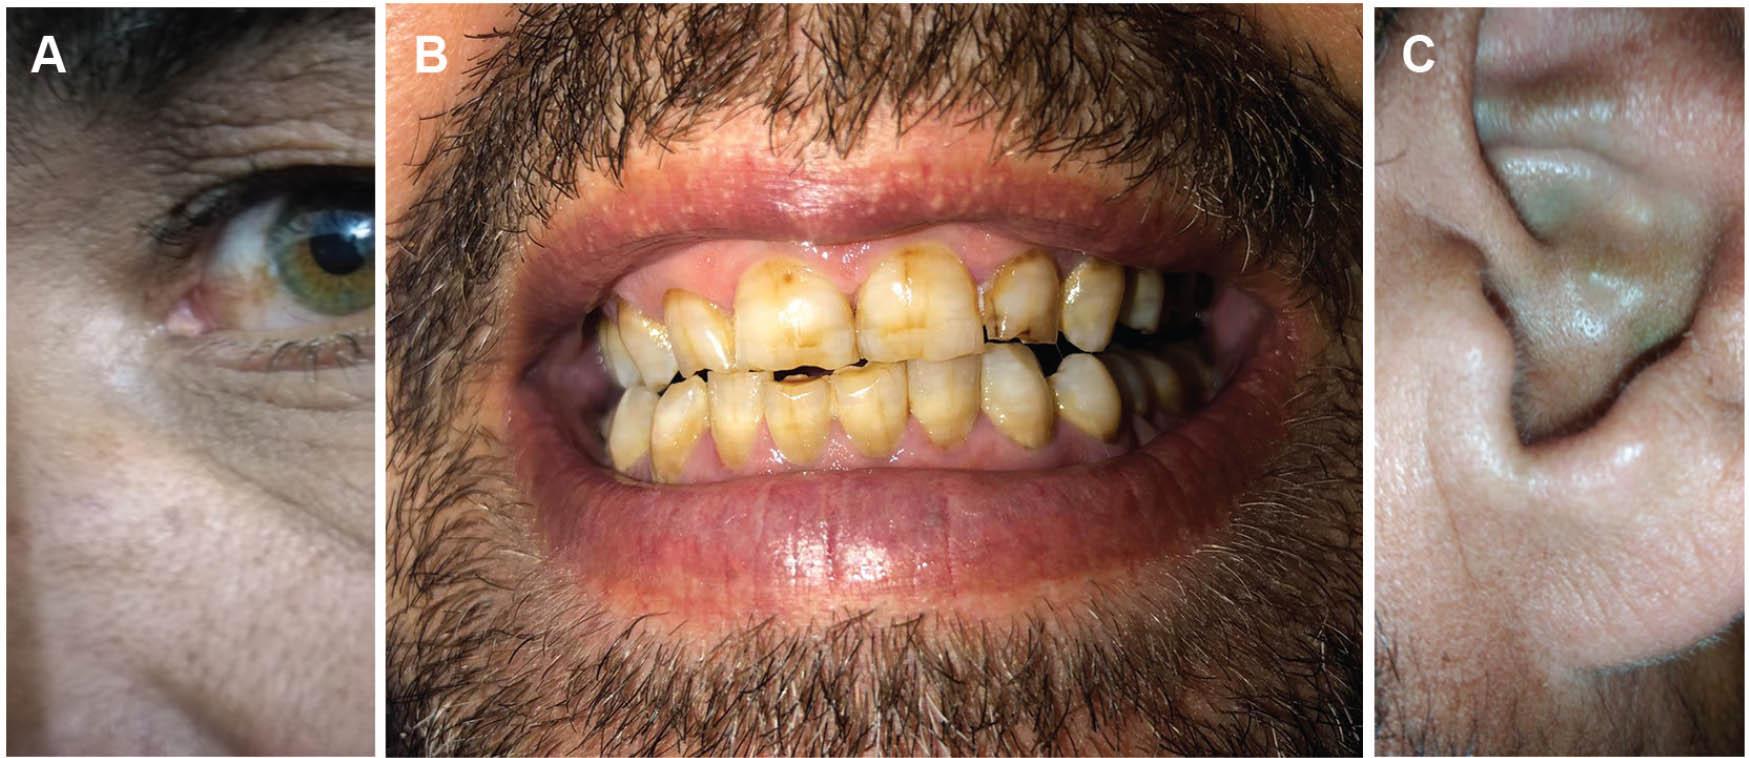

A 43-year-old man living in southern Jordan presented to our clinic in March 2019 with sudden onset of left Achilles tendon pain with no history of prior trauma. He had developed progressive low back and knee pain for the previous 5 years, which was managed using nonsteroidal anti-inflammatory drugs. He was diagnosed with alkaptonuria 10 years earlier (urine analysis and biochemical testing confirmed the HGA-uria at the time of diagnosis). The patient had discoloration of his teeth, ear pinna, and sclera of the eye (Figure 1), and his urine has been dark since childhood (Figures 2C, D). His sister and brother have been also diagnosed with alkaptonuria, and his parents are related (consanguineous marriage). Genetic analysis identified a homozygous missense variant c.365C>T lies in exon 6 of HGD resulting in the substitution of the amino acid alanine (Ala) with valine (Val) Ala122Val (SNP ID rs544956641) [17] (Figures 2A, B) as deposited in the HGD mutation database [4].

Figure 1

Clinical manifestations of alkaptonuria presented in the reported case. (A) Brownish discoloration of the eye sclera, (B) discoloration of the teeth, (C) bluish discoloration of the ear pinna. With documented consent for publication from the patient.